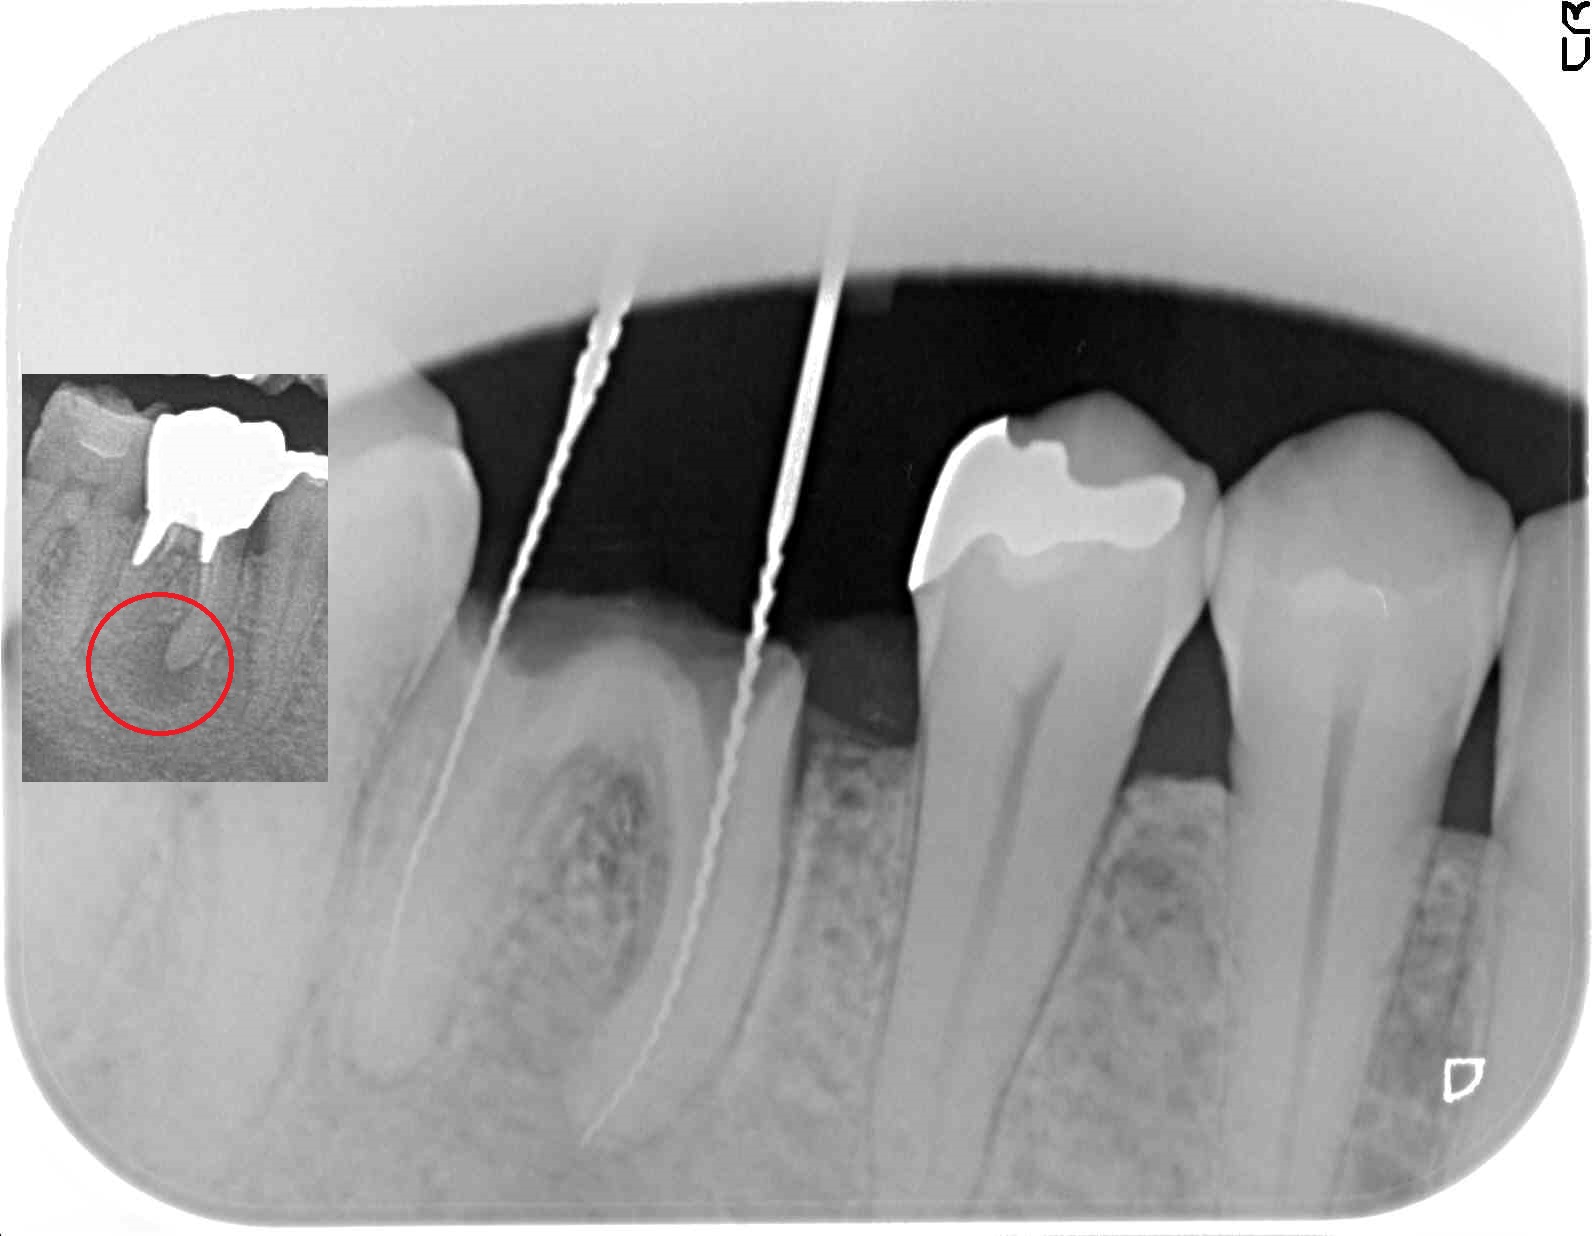

根の治療再発

上写真赤丸は、他院治療の直径5MM以上の病巣。

原因は、根の先端までの洗浄不足。

マイクロ、マイクロエキスカ使用で正確に先端まで根の治療をやりなおす。

先端まで隙間なく薬を詰め、病巣も消失。